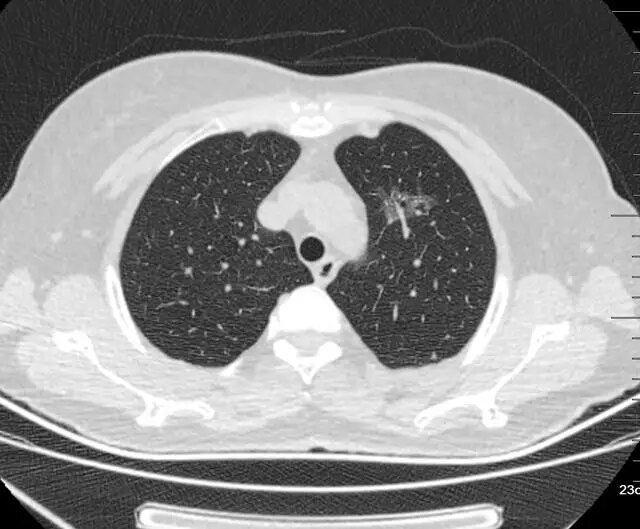

1、小毛刺结节

需要警惕磨玻璃结节的边界,正常良性结节都是有规则的边缘,看起来也是很清晰的,但是如果恶变那么边界就不会规则,还会有一些细小毛刺。